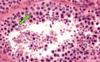

Alpha and beta cells in islet of Langerhans

Allows differentiation bw alpha and beta cells in islet of Langerhans. Beta cells stain more purple, alpha cells stain more pink. Most cells are beta cells, especially the ones in the middle

Beta cells in pancreas

Stains the insulin that is secreted by beta cells, beta cells stain darker